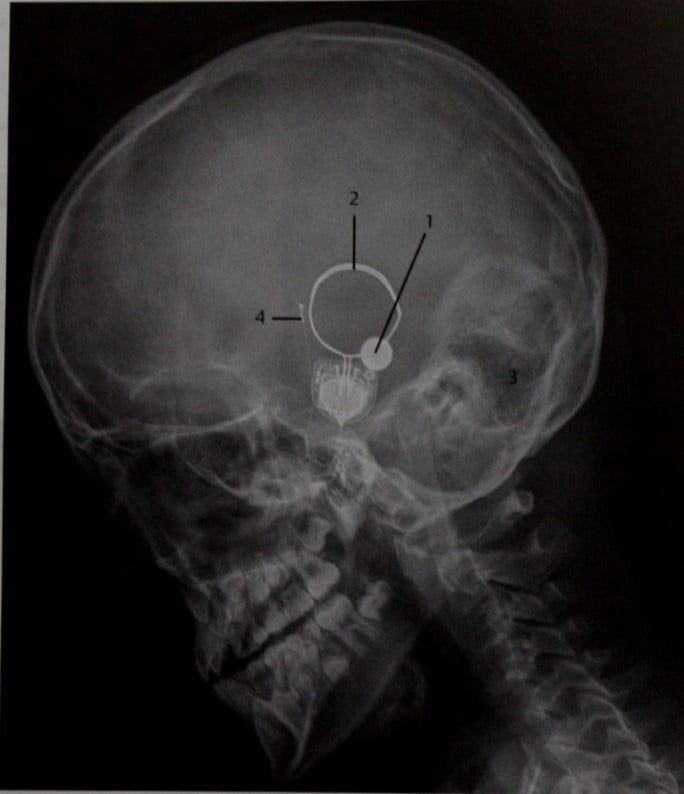

Рентгенография черепа и позвоночника: изображение и диагностика